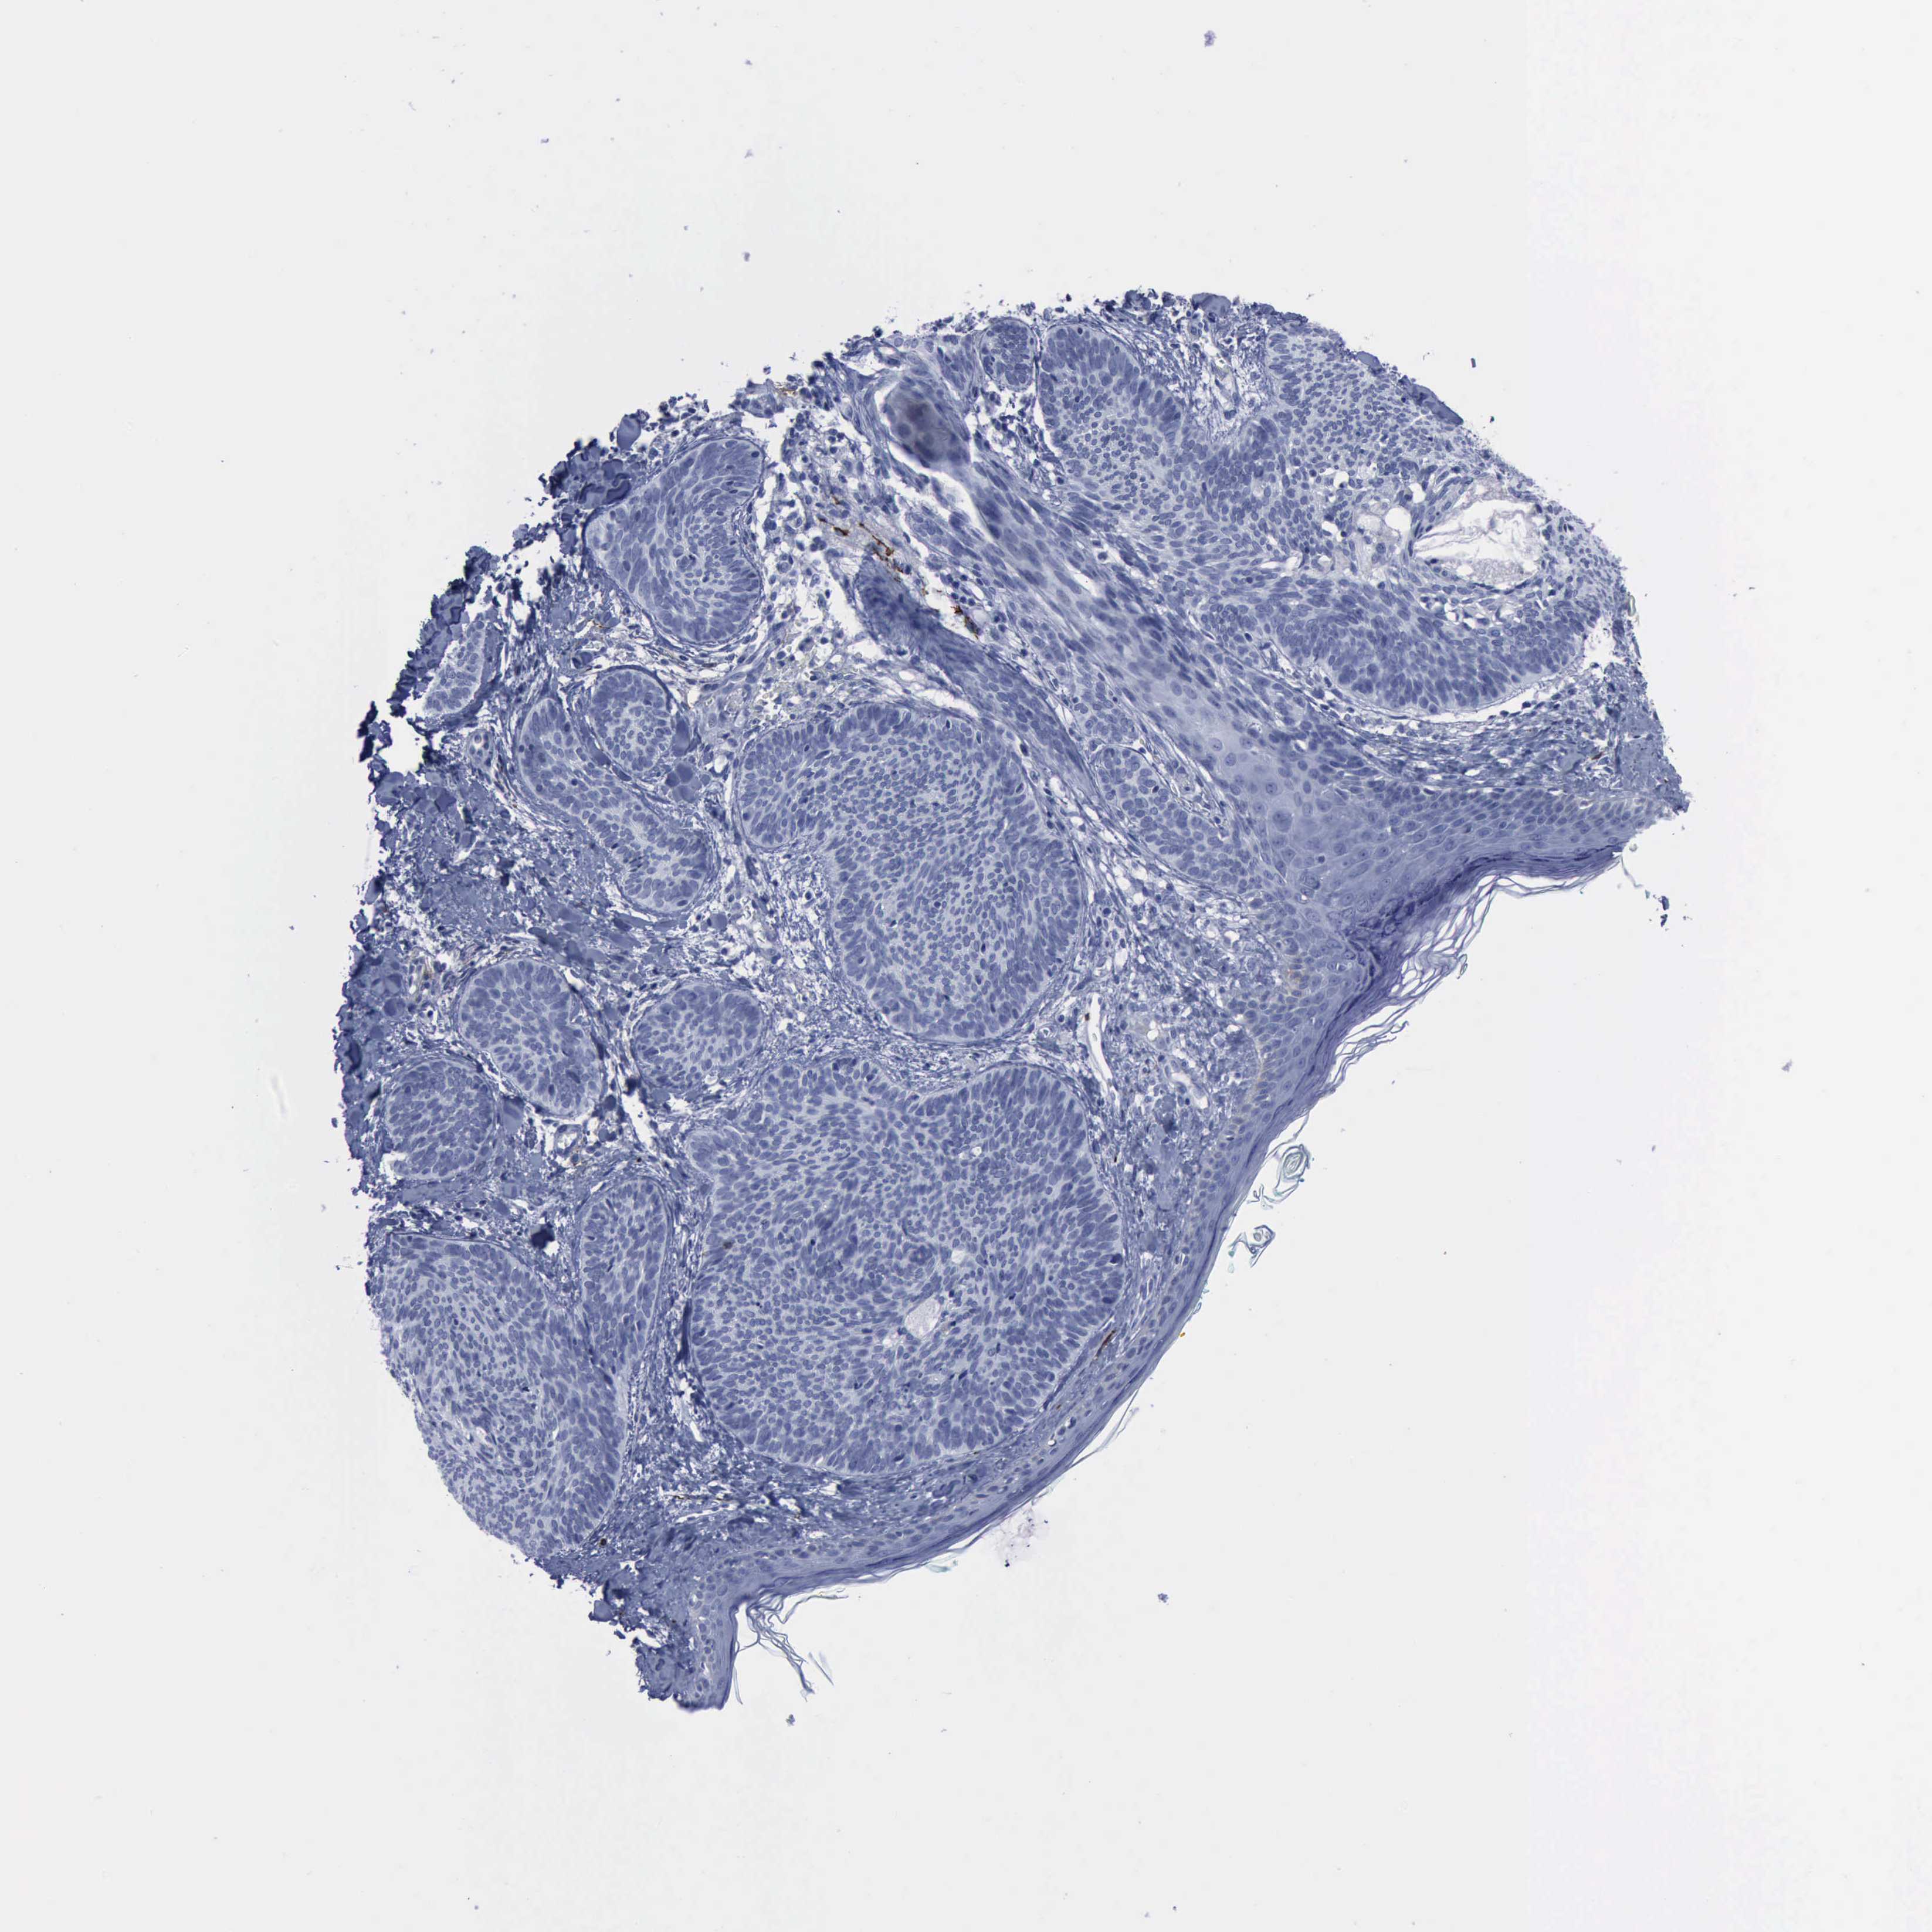

SKIN CANCER - Protein expressioni

A mouse-over function shows sample information and annotation data. Click on an image to view it in a full screen mode. Samples can be filtered based on level of antibody staining by selecting one or several of the following categories: high, medium, low and not detected. The assay and annotation is described here.

Antibody staining in the annotated cell types in the current human tissue is reported as not detected, low, medium, or high, based on conventional immunohistochemistry profiling in selected tissues. This score is based on the combination of the staining intensity and fraction of stained cells.

Each image is clickable and will lead to virtual microscopy that enables deeper exploration of all samples and also displays staining intensity scores, fraction scores and subcellular localization as well as patient and tissue information for each sample.

Antibody HPA004765

Squamous cell carcinoma, NOS